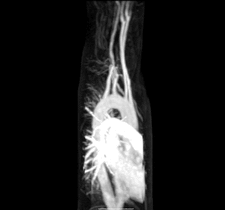

Lusory artery is aberrant branch of a. subclavie. It withdraws as the last branch of the aortic arch behind the left subclavian artery, or from the descending part of the aorta. It passes through the rear mediastinum usually behind osesophagus and because of the pressure caused by the oesophagus it can cause dysfagic problems (ie. dysphagia lusoria), it cen exceptionally pass between oesophagus and trachea and compress the respiratory tract and cause prolonged cough of infants. It can also press on n. laryngeus recurrens sinister and lead to Ortner's syndroms. Aberrant branch can also be associated with the so-called Kommerell's diverticulum.